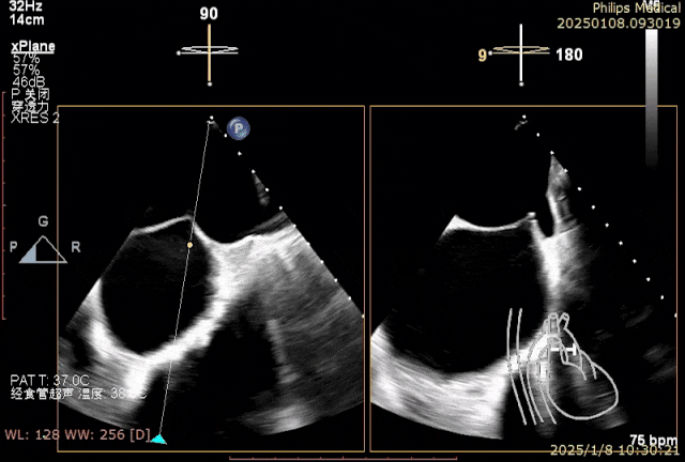

术中二尖瓣夹系统释放完毕

一切准备就绪后,麻醉手术中心专家凭借精湛技艺,让患者全程处于平稳麻醉状态,为手术筑牢安全根基。超声诊断科医生犹如“透视眼”,实时提供精准影像指引,让手术操作有的放矢。术中,陈玺全副主任团队在2区植入一枚长宽夹后,棘手状况再现。由于瓣叶张力过大,团队果断调整策略,以特定角度释放二尖瓣夹。当夹子关闭至-30°时,奇迹发生,反流降至1+,术后跨瓣压差仅为1mmHg,手术效果惊艳众人。